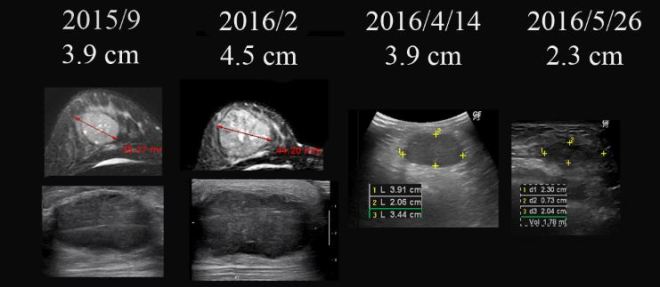

12강에서 다루려고 하는 환자의 case는 이미 7강에서 다루었던 환자의 이야기이다. 이와 더불어서 유방암의 주 공식인 AC+ Taxol의 항암 방법이 체질에 따라서 연구되어서 바뀌어야 한다는 생각을 한다. 이 환자는 7강에서 이미 이야기하였듯이 수술 전에 태음인이 AC 항암방법을 사용하고 나서 더 종양이 커져서 내원한 분이다. 초기 유방암 발견을 한 2015년 9월부터 나름대로 민간 요법을 하였는데 종양이 커지자, 할 수 없이 병원을 선택하였고 수술 전 AC 항암방법으로 더욱 커져서 내원하였다. 그리고 나의 권고대로 한약을 사용하고 나서 바짝 줄어드는 기미가 보이자 AC 를 4차까지 진행하지 않고, 병원을 바꾸어서 방사선과 Taxol을 6차까지 마쳤다. 그리고 방사선치료를 2016년 8, 9월 동안 시행하였고 이제 본원에서 치료 시작한지 1년이 지났고, 작년 9월 방사선 치료가 끝나고 나서 10월달 종양의 흔적 정도가 남아 있었다. 그리고  2017년 5월, 몇 일 전에    7 개월만에 다시 초음파 체크를 하였다. 그간 이 환자는 본원의 한약과 tamoxifen 요법을 지속하였고, 현재 수술은 안 한 상태이다. 암에서 수술이 초기에는 중요하다고  하지만 수술을 안 할 수 있으면 안 하는 것도 좋은 방법이 된다. 다만 이는 권하는 의사에게 매우 부담이 된다. 꼭 결과가 좋을 수는 없기 때문이다. 이 환자는 치료가 1년밖에 안 되었지만 현재 결과는 매우 좋다. 이러한 결과에 대한 설명을 하기 전에 먼저 수술을 하고 항암과 한약을 결합하여서 완치까지 끌고 나가기 위해서는  몇 가지 전제가 필요한데 이 환자와 같은 태음인은 거의  좋은 결과를 가지고 오고, 완치될 가능성이 높다. 그래서 이러한 가능성의 여부와 체질별 문제점을  다루고 나서 이 환자의 이야기를 다시 해 보려고 한다.

이야기를 본론으로 돌아가서 다시 해 보자. 이미  7강에서 실었던 원고를 그대로 옮기고 마지막 5월 중의 검사와 비교해 보겠다.

7-001

오늘 다루려고 하는 환자는 이전 6강에서 이야기하였듯이 항암제를 수술 전에 잘 사용하였을 때 종양을 잘 줄일 수 있고 이렇게 종양이 줄어든 상태에서 수술이든, 아니면 여타의 치료로 좋은 결과를 모색해야 하는 문제를 다루어 보려고 한다.

• 2015년 9월 유방암 발견  3.9 cm. 민간요법

• 2016년 2월 유방암 더욱 커짐  3.9cm  —-> 4.5 cm

• 2016년 2월 – 3월  #2차  AC  (adriamycin+cyclophosphamide) 요법 시행

• 2016년 3월 29일  본원 내원 종양  5cm 가량 약간 커졌음

• 2016년 4월 14일  본원  한약조치 이후  5cm의 종양  3.9 cm로 줄어들음

• 2016년 4월 15일  tamoxifen + 한방약물조치

• 2016년 5월 9일  1차  taxol  항암 시작함.  3.9cm(2016/4/4)  —-> 2.3cm (2016/5/26)

• 2016년 7월 8일  3차  taxol  항암 마침.  방사선 치료 의뢰

• 2016년 8월 – 9월 방사선 치료

• 2016년 9월 8일  2.3cm(2016/5/26) —-> 1.13cm(2016/9/8)

• 2016년 10월 13일 약 10mm  x 2mm의 종양의 괴사된 흔적 남아 보임

• 2017년 1월 16일 종양 완전소실  4.4×2.1mm의 흔적남음

• 2017년 5월 26일 초음파상 종양완전소실  2.4mm의 양성으로 보이는 흔적남음

• 수술 시행하지 않고 한약과 tamoxifen 요법을 지속함

7-002

이 환자는 한방요법과  타목시펜 그리고 2차 택솔요법 이후에 초음파상에서 장경 3.9cm (2016/4/14)이 2.3 cm(2016/5/26) 이후 7월, 8월 사이에  방사선 치료를 권하였다.

방사선을 해 주시는 교수님께서 내심 원격 전이가 없고 림프절 전이도 없는 초기 환자라 부담을 안고서 환자에게 “거의 완치율이 높은 경우인데 수술을 하고 와서 방사선 치료를 받는 것이 어떠냐” 라고 권유하였지만 다음날 환자가 마음이 굳어서 수술 전에 방사선을 해 보겠다고 이야기하니 환자 마음이 굳은 것을 확인하고 방사선 치료를 해 주셨다.

이후 방사선이 끝나고 내원하여 9월 달 보니 종양의 거의 괴사되어서 1.13×0.58cm의 크기가 남아 있었고 한달 뒤인 2016년 10월 13일에는 1.03×0.2cm 정도의 괴사된 흔적만 보였다.

이 환자는 아직 치료 시작단계이지만 앞으로 3년 한약과 tamoxifen 을 병행하고 이후에 5년까지는 겨울 3개월 한약을 권유하고 tamoxifen 은 총 8년 도 복용할 것을 권유하였다. 아마도  나의 이제껏 경험으로는 재발은 없으리라고 예측한다.

그래서 초기 자료와 비교를 해 보면 다음과 같다.

이후한방치료와 tamoxifen 요법을 병행하면서 위의 결과와 같이 양성의 흔적만 보인다.